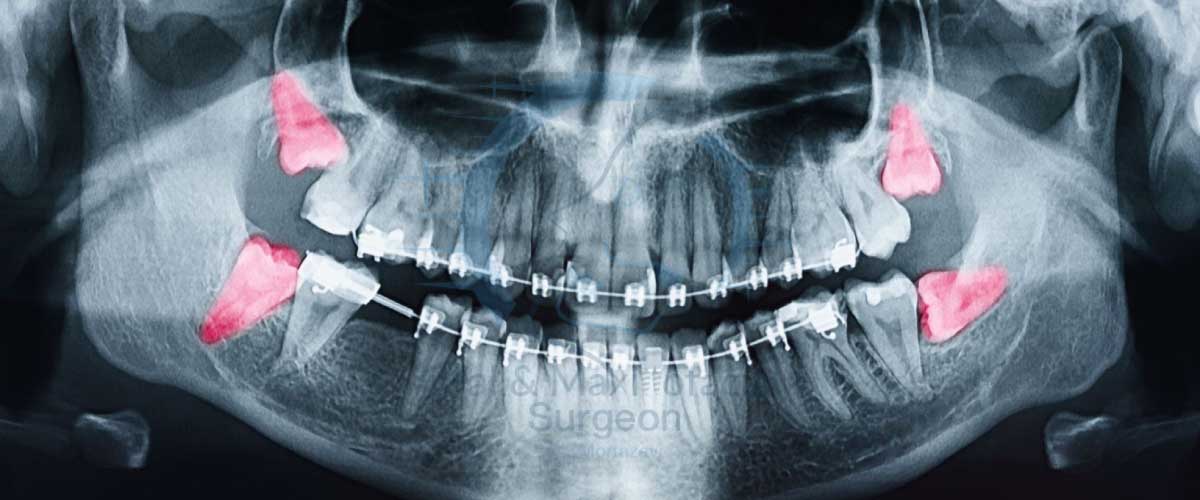

- نامرتب شدن سایر دندانها: فشار ناشی از دندان عقل نهفته میتواند به تدریج باعث جابجایی و نامرتب شدن دندانهای دیگر شود و تمامی زحمات ارتودنسی شما را از بین ببرد.

- کاهش فضای مناسب برای رویش: گاهی اوقات، دندانپزشک با مشاهده عکسهای رادیوگرافی و ارزیابی فک، پیشبینی میکند که دندان عقل به دلیل کمبود فضا نمیتواند به درستی رویش کند. در این موارد، ممکن است کشیدن پیشگیرانه برای جلوگیری از مشکلات آینده توصیه شود.

قبل از هر اقدامی، دندانپزشک شما را معاینه کرده و یک عکس رادیوگرافی (مانند OPG) از فک شما تهیه میکند. این عکس به دندانپزشک کمک میکند تا وضعیت دقیق دندان عقل، ریشه آن، و نزدیکی آن به عصبها یا حفرههای سینوسی را ارزیابی کند. در این مرحله، تمامی گزینههای درمانی و خطرات احتمالی با شما در میان گذاشته میشود. توجه کنید درصورتی که دندان عقل نهفته باشد حتماً میبایست تصویر cbct نیز تهیه شود. این تصویر محل دقیق ریشه دندان عقل را مشخص میکند و از عوارضی مانند بیحس شدن لب که ممکن است بعد از کشیدن دندان عقل به وجود بیاید، جلوگیری میکند.